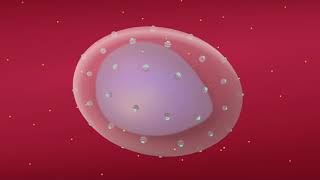

Red Blood Cell Invasion by Malaria Parasites | Manoj Duraisingh

Red Blood Cell Invasion by Malaria Parasites | Manoj Duraisingh Understanding How Malaria Parasites Take Over Human Red Blood Cells

Red Blood Cell Invasion by Malaria Parasites | Manoj Duraisingh

Red Blood Cell Invasion by Malaria Parasites | Manoj Duraisingh Understanding How Malaria Parasites Take Over Human Red Blood Cells